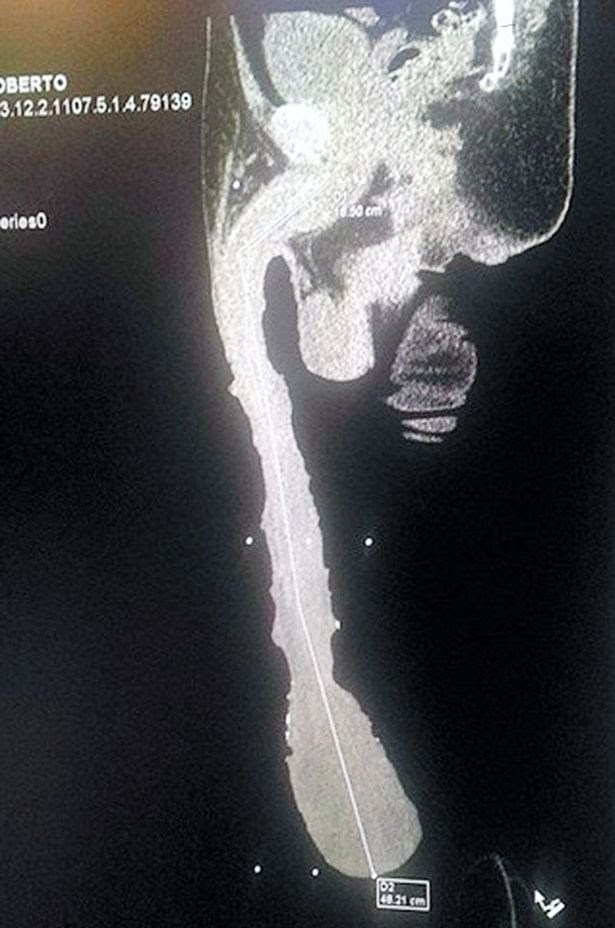

Roberto Esquivel Cabrera navodno je muškarac koji ima najveći penis na svijetu, a dužine 48 cm.

Rentengska snimka pokazuje nešto što bi moglo potvrditi njegovu priču, a kaže i da se prijavio u Guinnessovu knjigu rekorda.